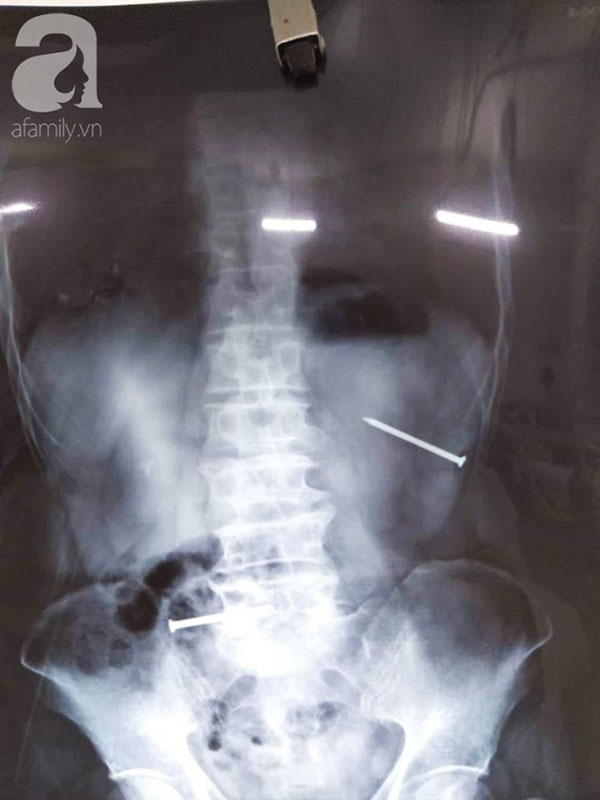

Người đàn ông 57 tuổi, ngụ Dĩ An, Bình Dương nhập khoa Cấp cứu trong tình trạng đau bụng dữ dội, chảy máu thành bụng, choáng. Bệnh nhân có 2 cây đinh đâm xuyên thành bụng, trong đó một chiếc đâm sâu vào lỗ rốn.

Bệnh nhân được chuyển sang phòng mổ tiến hành mổ nội soi thám sát. Kết quả nội soi cho thấy dù mũi đinh đâm xuyên thành bụng, vào tới ổ bụng nhưng rất may mắn bệnh nhân không bị thủng các tạng tại vị trí đó như: dạ dày, ruột non hay đại tràng góc lách.